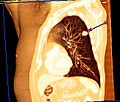

Der Unterschied zwischen der überlagerungsfreien Darstellung in der medizinischen Tomografie und einer Projektionsabbildung ist in den nachfolgenden Abbildungen illustriert. In Projektionsverfahren wie der Radiografie (gewöhnliche Röntgenuntersuchung) wird ein Schattenbild aufgenommen, auf dem sich mehrere Strukturen überlagern, wenn sie im Strahlengang hintereinander liegen. Beispielsweise überlagern beim konventionellen Röntgenbild die Weichteile der vorderen und hinteren Brustwand und die knöchernen Strukturen des Thorax die Lungenstrukturen. Dies würde die Diagnose eines Lungentumors (z. B. Bronchialkarzinom) erschweren. Jedes CT- oder MRT-Schnittbild vom Thorax zeigt dagegen nur eine 0,5 bis 10 mm dicke Schicht, die praktisch überlagerungsfrei ist.

Derselbe Tumor in der Computertomografie (axiales Schnittbild) -